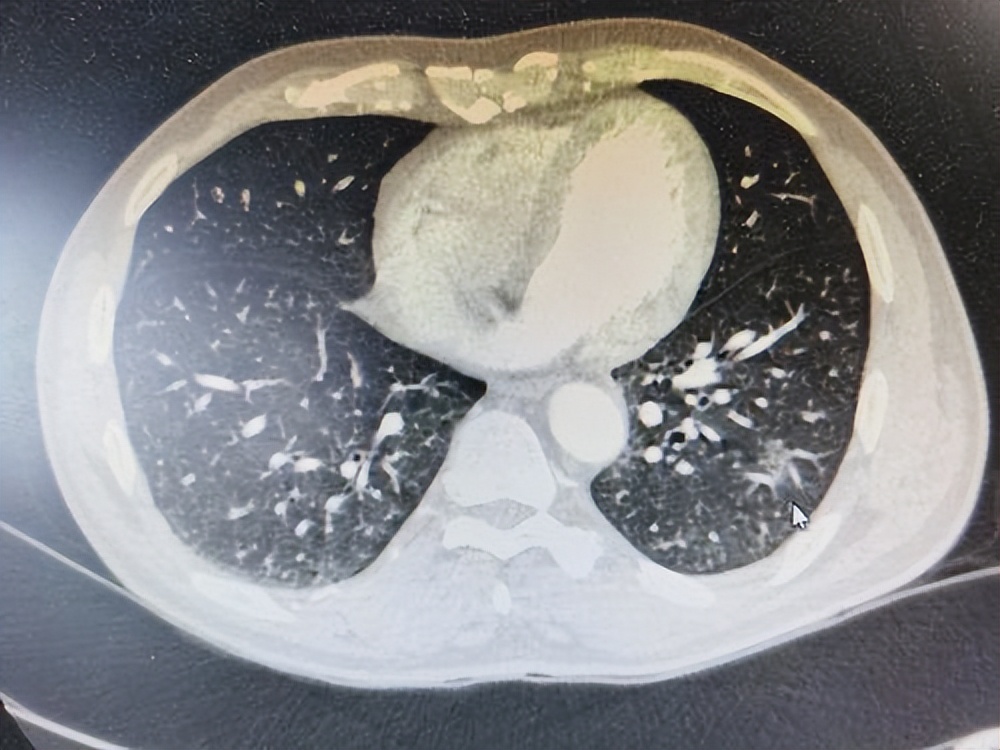

知识拓展——“肺要咳出来了”,是不是应该去医院拍个CT?

复旦大学附属中山医院重症医学科主任钟鸣:如果单纯是刺激性的干咳,并不代表有肺炎。因为如果有肺炎的话,还有气急、胸闷这种感觉。很多时候上呼吸道感染,可能是上呼吸道的一个炎症和损伤的过程。

这个状态下,很容易感觉到有异物感,很容易咳嗽,这都是上呼吸道有炎症和受损伤的表现。炎症的消退和上呼吸道受损黏膜的修复,需要时间,在修复之前你可能一直会有干咳,这都是很常见的。

所以短时间的,可以去等待自愈,如果咳嗽非常明显,影响到生活质量、睡眠、日常工作,可以用镇咳的药去缓解症状。但需要提醒的是,有些时候这些急性炎症如果没有完全修复好,会变成上呼吸道的慢性炎症,咳嗽会变成很迁延的症状。

良好的免疫系统很重要,建议在转阴的这段时间里,也要有规律的作息,让你身体保持在比较好的状态,尽量去修复之前损伤的部位,包括上呼吸道。也不是鼓励完全卧床,适当的运动加上营养,有利于康复。

如果咳嗽伴有痰,每次都有很多痰,这可能就不仅仅是上呼吸道炎症的问题,还可能涉及到支气管或肺部,特别是咳出来大量的黄浓痰时,建议要到医院去看。